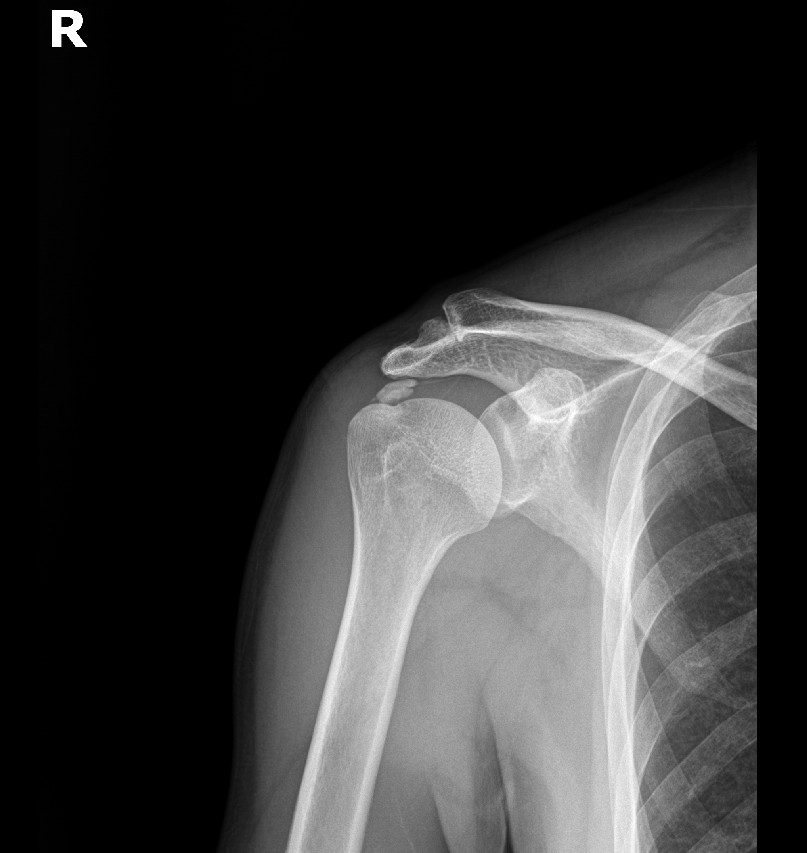

케이스 1: 형성기 단단한 석회 (1회 제거)

환자: 50대 남성, 우측 어깨 통증 8개월

시술 전:

X-ray에서 약 1.5cm 크기의 석회 확인

형성기 석회 (매우 단단)

타 병원에서 "수술 권유" 받음

시술 후:

1회 분쇄흡입술로 완전 제거

시술 직후 X-ray에서 석회 없음 확인

진단:

X-ray: 약 1.3cm 석회 (휴지기)

시술 직후 X-ray에서 석회 완전 제거 확인